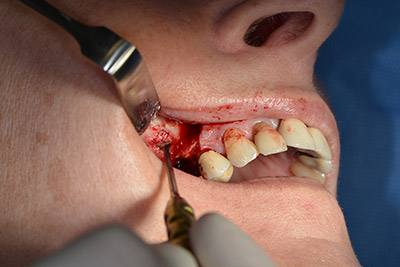

Die 59-jährige Patientin wurde mit einer fortgeschrittenen Parodontitis vorstellig, beschrieb ein ungutes Gefühl und einen schlechten Geschmack ausgehend vom ersten Quadranten distal. Die klinische Untersuchung zeigte allgemein erhöhte Taschentiefen und einen stark fortgeschrittenen Knochenabbau in regio 16 und 14. Die radiologische Untersuchung untermauerte den Befund (Abb. 1). Die Zähne 16 und 14 waren nicht zu erhalten.

Abb.1: Orthopantomogramm mit Knochenabbau in Regio 16–14.*